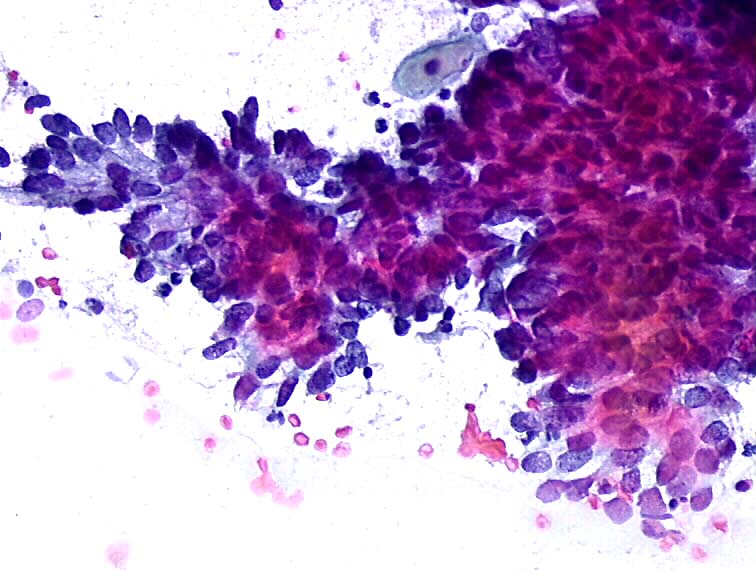

❗Что такое цитологическое исследование:

Это оценка характеристик морфологической структуры клеточных элементов с целью установления диагноза доброкачественной или злокачественной опухоли и неопухолевых поражений.

Отличие цитологического исследования от гистологического заключается в том, что изучаются не срезы тканей, а клетки.

Другими словами, берутся клетки тканей и рассматриваются под микроскопом, а лаборант должен определить, какие это клетки — плохие или хорошие и, если плохие, к какому виду злокачественных клеток они относятся.

То есть некоторым образом за достоверность анализа отвечает и человеческий фактор.

В любом случае, цитологическое исследование менее травматично, нежели гистологическое, где нужно отрезать кусочек ткани для исследования. Но и менее информативное по сравнию с обычной биопсией, где исследуются ткани.

Маме делали абразивное исследование, то есть просто поскребли место опухоли и отправили материал на исследование.

К сожалению, анализы по цитологии пришли неутешительные. Как написано в заключении — «Вероятно, плоскоклеточный рак»

Но, как оказалось позже, анализ оказался неверным, и у мамы была другая форма рака, которая была гораздо хуже и требовала совершенно другого подхода во взятии анализов и дальнейшего лечения.

👉В общем, цитологическое исследование может помочь в постановке диагноза, но ни в коем случае не стоит верить ему безоговорочно. Оно достаточно информативно в самом начале, когда опухоли как таковой еще нет, но если даже и обнаружены злокачественные клетки в анализе, обязательно нужно перепроверять, так как ошибка очень сильно может повлиять на дальнейший ход развития событий. У нас из-за ошибочной интерпретации злокачественных клеток в дальнейшем была взята биопсия части опухоли, что делать при этой форме рака категорически нельзя.